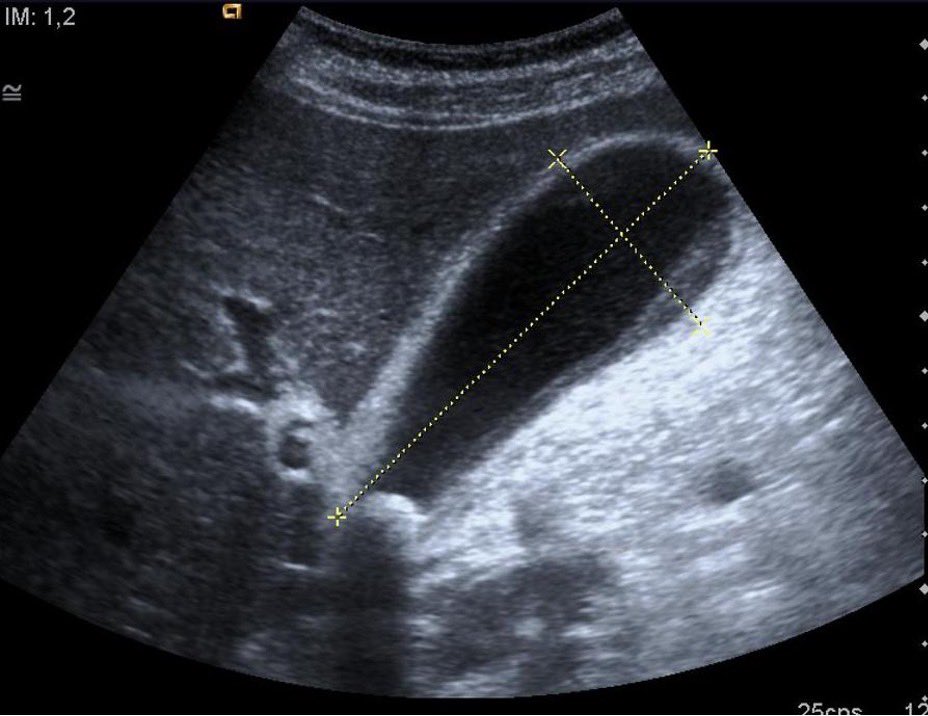

Gallbladder hydrops: size of GB  > 4 cm (transverse) x > 9 cm (longitudinal) • Most commonly caused by impacted gallstones (at neck) • Prolonged blockage of cystic duct leads to increased intraluminal pressure, inflammation > High suspicion of cholecystitis (surgery consult)

Gallbladder hydrops: size of GB  &gt; 4 cm (transverse) x &gt; 9 cm (longitudinal)

• Most commonly caused by impacted gallstones (at neck)

• Prolonged blockage of cystic duct leads to increased intraluminal pressure,  inflammation

&gt; High suspicion of cholecystitis (surgery consult)